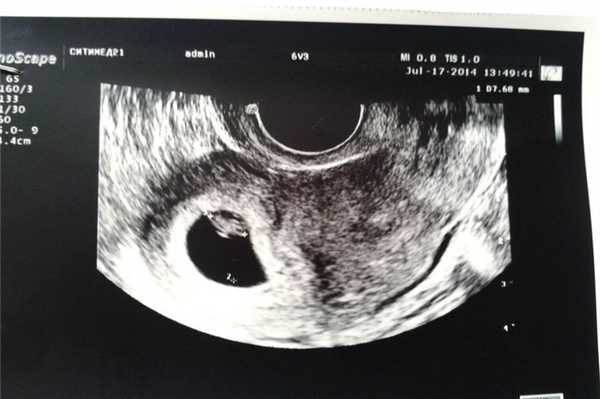

Данные ультразвука на 6 неделе

Плод активно растет. У него исчезает хвостик, формируется костная ткань, образуются нос и глаза. Ультразвуковое исследование обычно проводят при помощи внутривлагалищного датчика. Врач может услышать сердцебиение плода, а на фото отчетливо видно место прикрепления плодного яйца. Если беременность многоплодная, это видно на снимке. Также можно с высокой точностью определить дату зачатия.